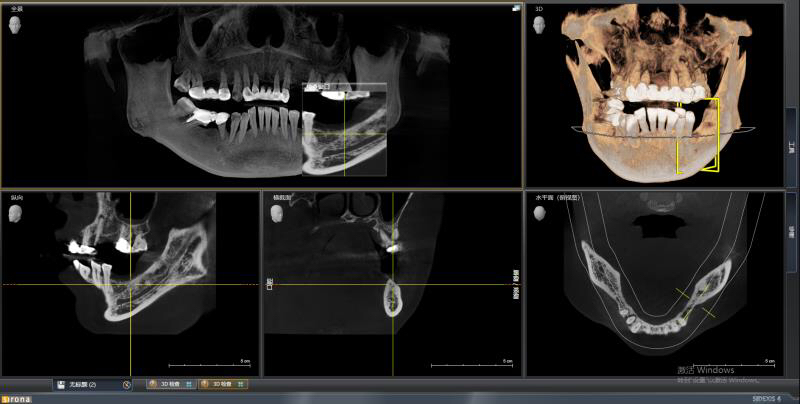

患者中年女性,左下5、6、7缺失多年,牙槽骨吸收较多,CBCT可见牙槽骨高度不足,距离下颌神经管比较近,所以为这位患者选择了短植体进行种植,术中植骨盖膜,历时7个月戴上了牙齿,患者使用满意。